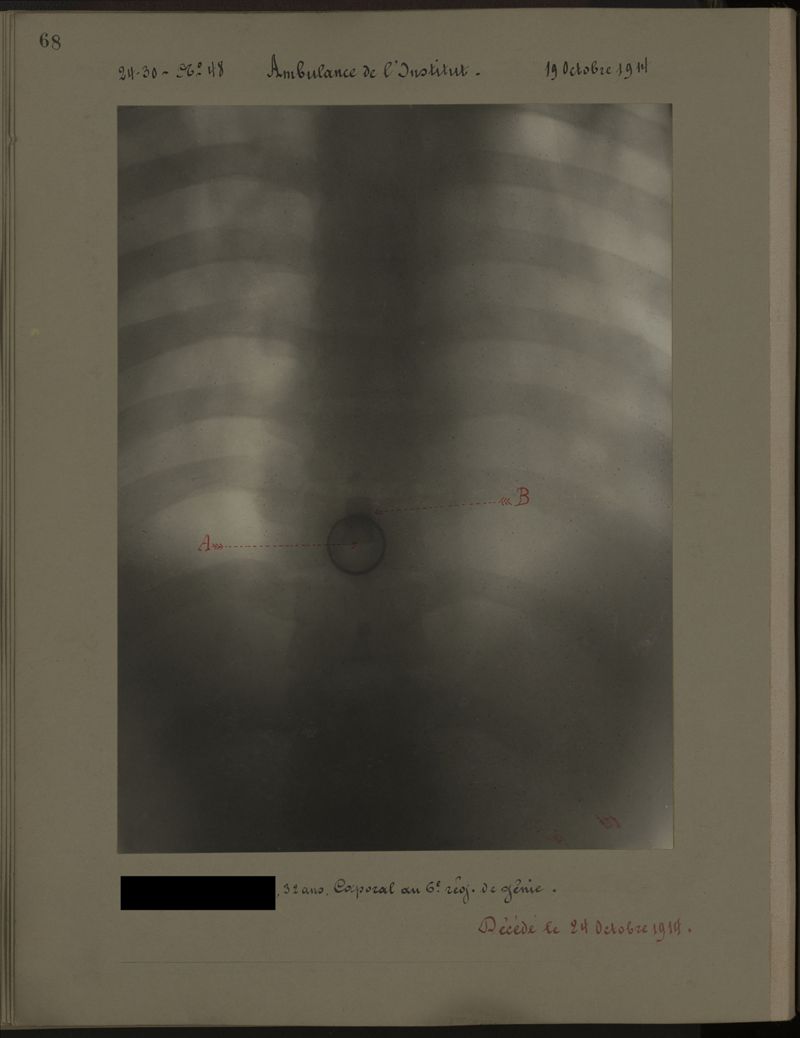

Deux albums de radiographies de la Première Guerre mondiale. Collection du laboratoire central de radiographie de la Salpêtrière. Deuxième album.

1915.